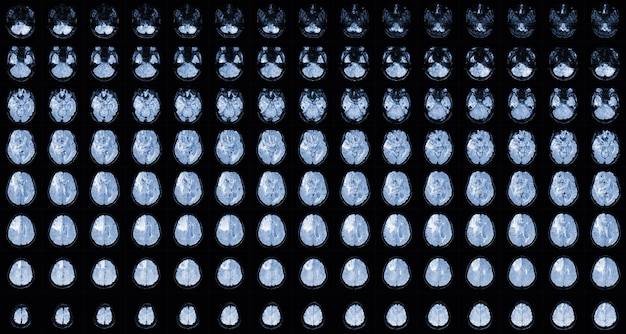

Tomografia z kontrastem, określana też jako TK z kontrastem, wykorzystuje promieniowanie rentgenowskie oraz jodowy środek cieniujący, aby zwiększyć różnice pochłaniania promieniowania pomiędzy tkankami. Dzięki temu na obrazie struktury docelowe stają się jaśniejsze lub ciemniejsze, co ułatwia precyzyjną ocenę narządów i naczyń [1][2][7].

Fizycznie wiązka RTG przechodzi przez ciało z różną intensywnością, detektory rejestrują dane, a komputer przelicza je na obrazy przekrojowe. Jod w kontraście zmienia pochłanianie promieniowania, co wzmacnia kontrastowość obrazu i pozwala lepiej wykrywać zmiany chorobowe [2][7].

TK z kontrastem zwiększa wykrywalność zmian, które w badaniu bez kontrastu mogą być słabiej widoczne. Szeroko wykorzystuje się ją w diagnostyce nowotworów, urazów oraz chorób narządów wewnętrznych [1][3].

Dzięki właściwościom jodu szczególnie dobrze uwidocznione są naczynia krwionośne, guzy i stany zapalne, co ułatwia planowanie dalszej diagnostyki i leczenia [2][3].

Zebrane dane są przeliczane na obrazy przekrojowe i rekonstrukcje, co pozwala na dokładną ocenę topografii zmian i ich relacji do istotnych struktur anatomicznych [1][5].